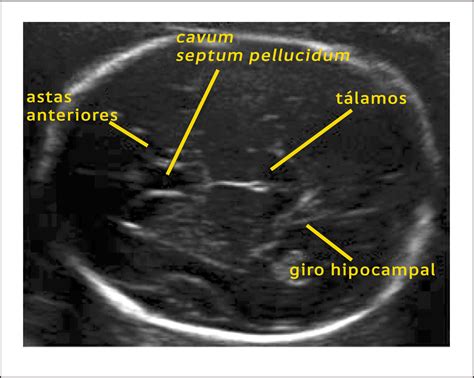

La forma tradicional de evaluar el tamaño del feto consistía en medir la longitud del útero. Sin embargo, actualmente el diagnóstico del CIR se realiza de manera habitual a través de una ecografía. Esta prueba de imagen permite detectar el estado de la placenta, el volumen de líquido amniótico, el peso estimado del feto y el diámetro de la cabeza, así como la circunferencia abdominal.

La microcefalia, por ejemplo, se diagnostica cuando la circunferencia de la cabeza del bebé es menor al promedio para su edad gestacional, específicamente al menos 2 desviaciones estándar por debajo del promedio o menor a la medida del 95% de los fetos de la misma edad gestacional.